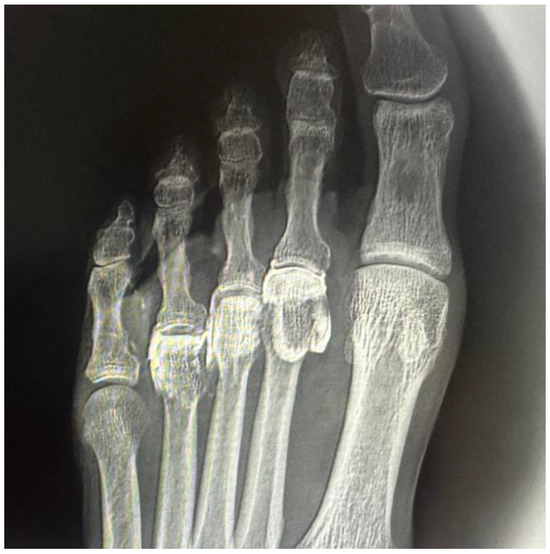

In all specimens, IM space infiltration resulted in diffuse, uncontained dispersion with irregular expansion and poorly defined borders (Figure 4). The contrast extended both proximally and laterally into adjacent soft tissue planes, following fascial paths with no clear anatomical containment. Additionally, a tendency for contrast migration toward the plantar region was observed, following the trajectory of the common plantar digital nerve. The mobility and superficial location of this nerve within the IM space appear to facilitate the lack of containment. This pattern confirms that the IM space functions as an anatomically open cavity with higher permeability to infiltrated fluid.

Figure 4. Ultrasound-guided injection of 0.5 cc of radiopaque contrast targeting the third common plantar digital nerve. The injection was performed in long axis, with a distal-to-proximal trajectory parallel to the nerve. (A) Dorsoplantar projection of the right forefoot. (B) Oblique projection of the same injection, allowing for better visualization of the contrast tracking along the interdigital space.